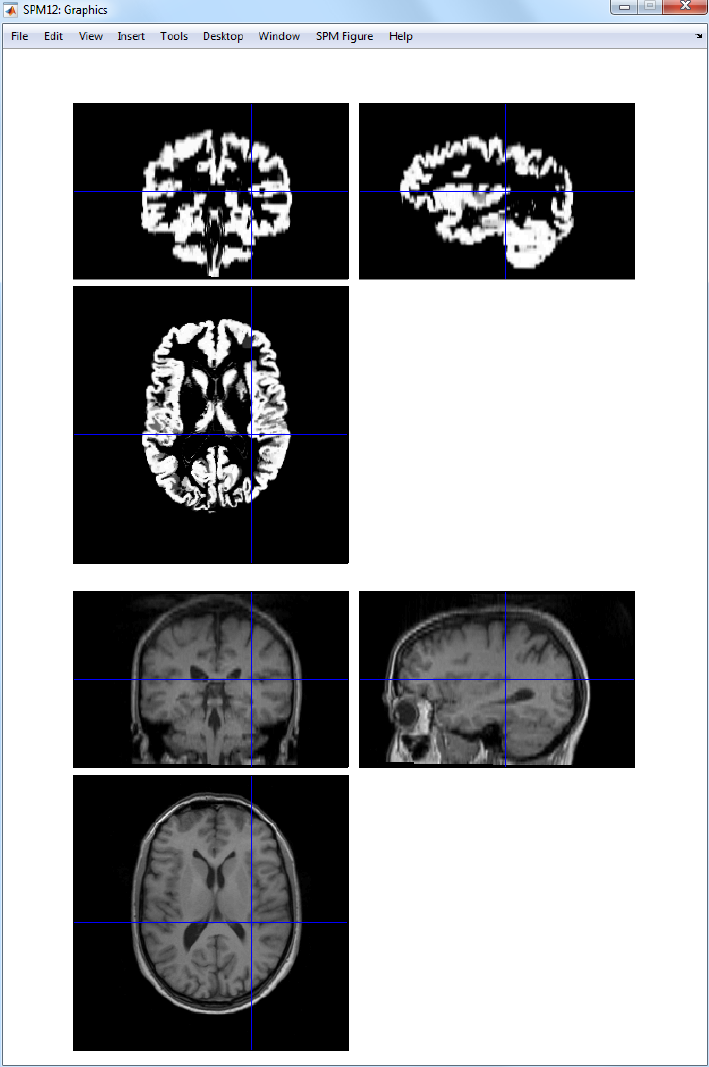

30.2.3 Segmentation ...................................223

31.1.5 Segmentation ...................................248